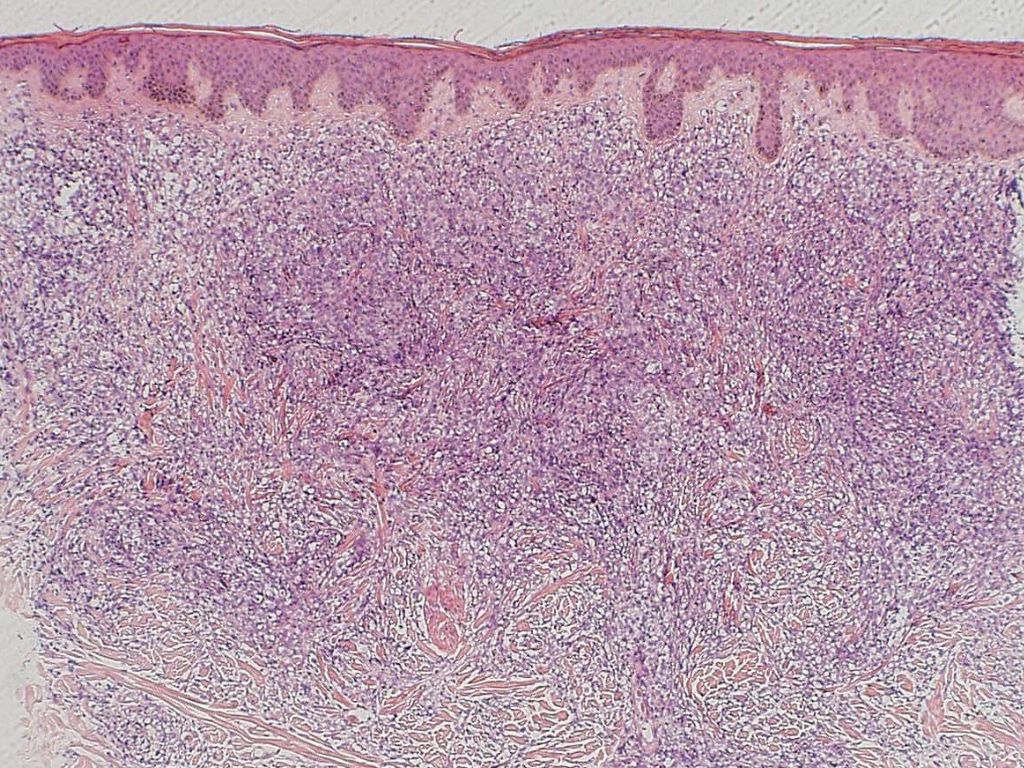

PA:

Epidermis geen afwijkingen. In de oppervlakkige dermis bevindt zich een dicht infiltraat van atypische lymfoïde cellen. De lymfoïde cellen tonen vergrote, blazige, gedenteerde kernen, meerdere mitose-figuren zijn zichtbaar. Tussen het infiltraat en de epidermis bevindt zich een vrije zone. De tumorcellen kleuren positief aan voor CD79a, en CD20 en negatief voor CD3. Met moleculair pathologisch onderzoek kan een clonale B-cel populatie worden aangetoond.

Dit type cutaan lymfoom komt vooral voor bij oudere patiënten (>70 jaar). Klinisch ziet men één of meerdere paarsrode tumoren op één of beide (onder)benen. Bij circa 10% elders op het lichaam. Histologie: diffuus infiltraat van centroblasten en immunoblasten, bcl-2, Mum-1 en Fox-P1 positief. Zie ook de ingescande PA-coupe van de afdeling pathologie van de University of Toronto.